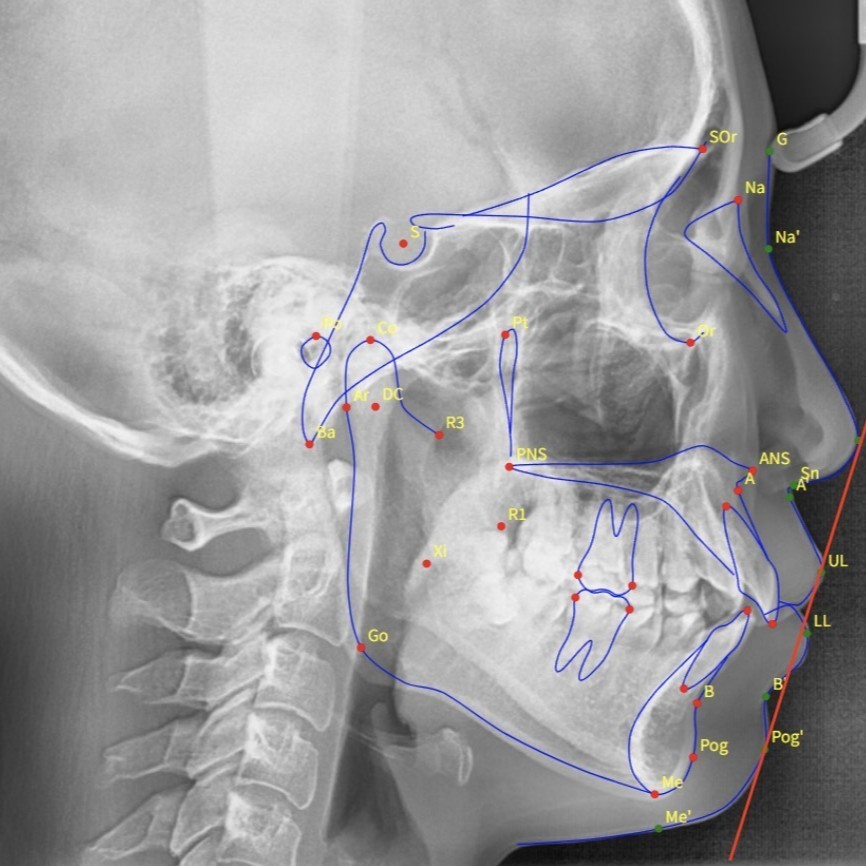

セファロ(頭部レントゲン)

また、パノラマレントゲン(歯列全体のレントゲン)だけで済ませて、セファロ(頭部レントゲン)を撮らない歯科医師も多いのですが、パノラマレントゲンだけでは、噛み合わせの正しい診断が下せません。

パノラマレントゲンではわからない、顎関節顎の骨などの骨格や、噛み合わせの状態を把握できるセファロの撮影をする歯科医師の方が安心できるでしょう。